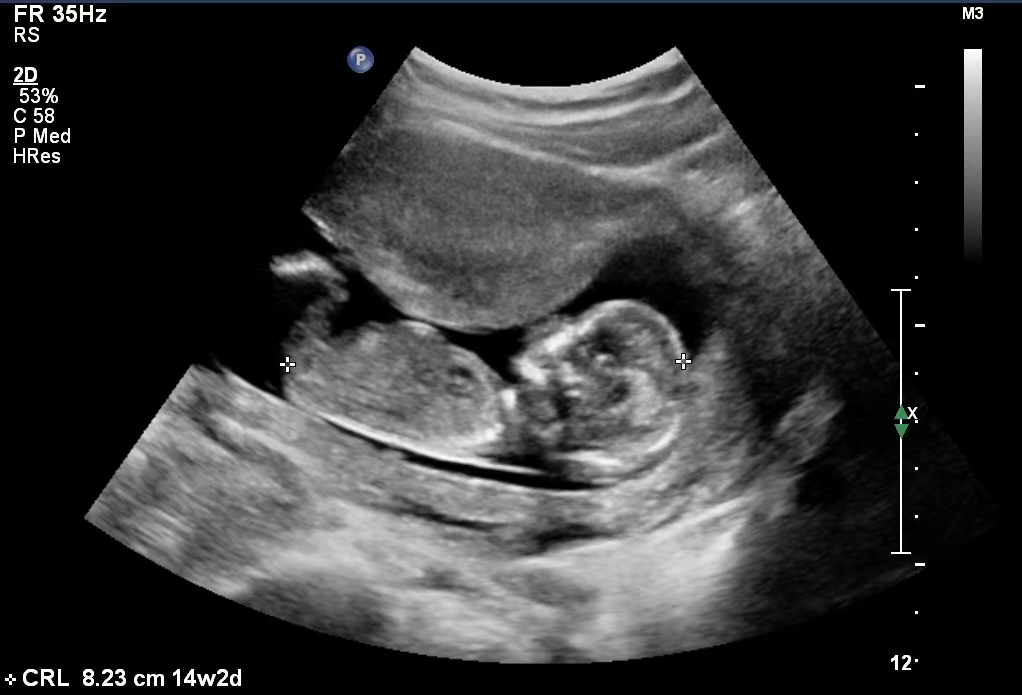

“MALBAC-Baby”在胎兒期B超圖

2014年9月19日,世界首例經MALBAC基因組擴增高通量測序進行單基因遺傳病篩查的試管嬰兒順利誕生。

2014年9月19日,世界首例“MALBAC-Baby”誕生